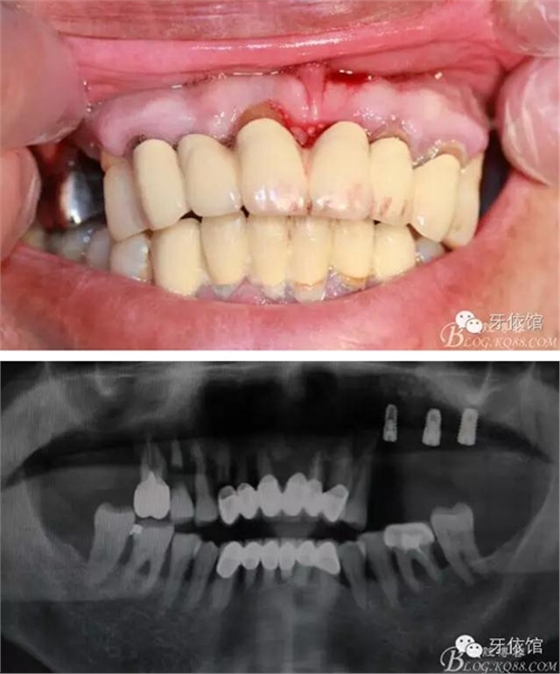

患者男,65歲,口內(nèi)多組烤瓷橋,具體時(shí)間不詳,左上5,6,7已于5個(gè)月前即可種植,OSS-TEM系統(tǒng),余留牙都已三度松動(dòng);此患者笑線(xiàn)高,微笑時(shí)唇緣在齦緣上4mm。

術(shù)前口內(nèi)照和X光片